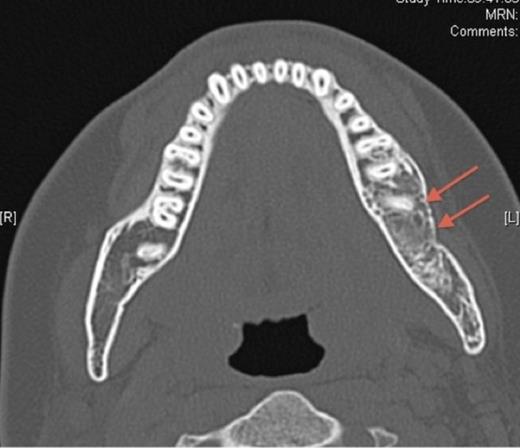

Pre-operative axial CT showing the lesion in the left side of the mandible (denoted by arrows).